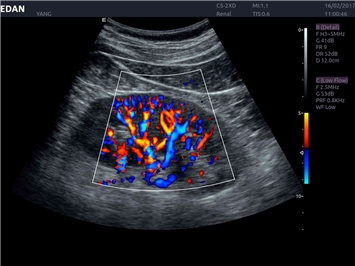

• Общей визуализации

• Акушерства и гинекологии

• Кардиологических исследований

• Сосудистой диагностики

Трехмерная реконструкция ЦДК:

Да

Энергетический допплер:

Color 3D: